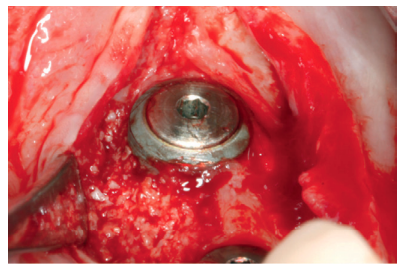

Anitua E, Carda C, Andia I. A novel drilling procedure and subsequent bone autograft preparation: a technical note. Int J Oral Maxillofac Implants 2007; 22: 138-145.

Anitua E. Plasma rich in growth factors: preliminary results of use in the preparation of future sites for implants. Int J Oral Maxillofac Implants 1999; 14: 529-35.